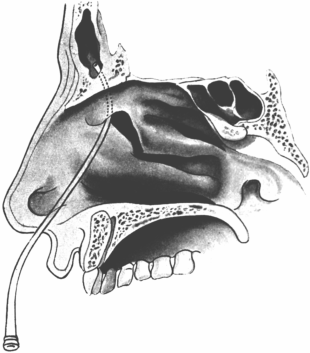

| 345. | Catheterizing the Sphenoidal Sinus | 654 |

| 344. | Radiograph of the Sphenoidal Sinus | 653 |

| 343. | Radiograph of the Sphenoidal Sinus | 653 |